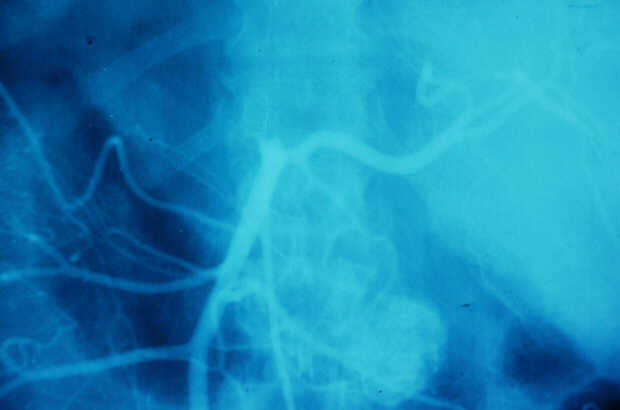

Diagnosis: Angiography

Giuseppe Morelli Coppola, Raffaella Niola, Franco Maglione

Unità Operativa di Radiologia Vascolare ed Interventistica, Azienda Ospedaliera "A. Cardarelli". Napoli, Italy